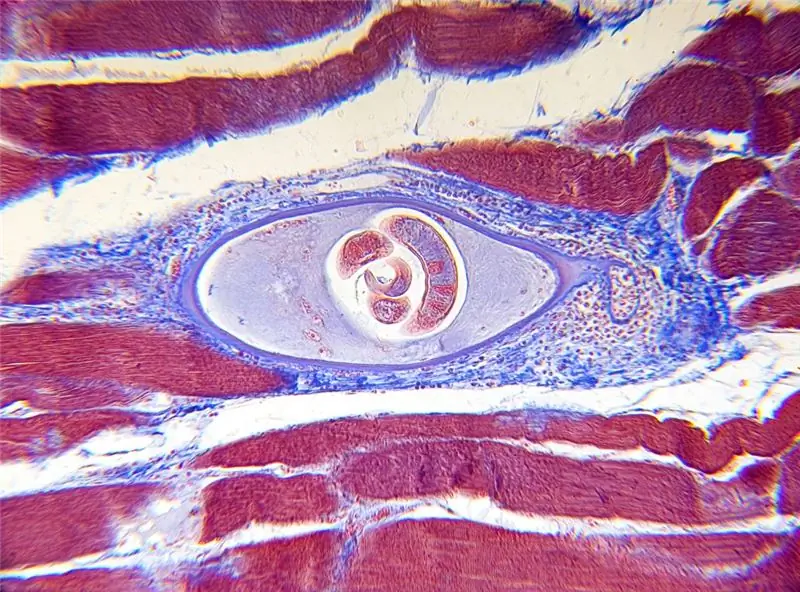

Ученые из Медицинской школы Университета Нью-Йорка сообщают о необычном эксперименте в научном журнале «Science Translational Medicine». Пациент проглотил яйца власоглава для лечения хронического заболевания кишечника. Этому предшествовали наблюдения научной группы под руководством P’nG Loke, согласно которым язвенный колит встречается значительно реже в некоторых странах, где широко распространены глистные инфекции. Другие исследования также показали, что глисты могут останавливать и уменьшать воспаление.

Для медицинского эксперимента пациент добровольно проглотил яйца власоглава (Trichuris trichiura). В ходе исследования ученые изучили показатели крови 34-летнего мужчины. Исследования проводились до и после употребления червей. Фактически, через несколько месяцев самочувствие пациента улучшилось. Исследователи обнаружили, что заражение червями вызвало размножение клеток иммунной защиты в организме пациента. В частности, в большом количестве образовался белок «интерлейкин 22». Белок отвечает, среди прочего, за стабилизацию и заживление слизистых оболочек. Исследователи подозревают, что заражение червем заставило иммунную систему сформировать больше защитных клеток, чтобы укрепить слизистые оболочки и поглотить червя. Другие медики подозревают, что глисты сами выделяют эффективные вещества. Эксперименты на животных показали, что этот метод может облегчить симптомы аутоиммунных заболеваний (например, астмы).

глистная инвазия Изображение: Carolina K Smith MD - fotolia